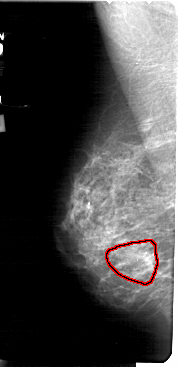

A_1730_1.LEFT_MLO

LEFT_MLO LINES 5491 PIXELS_PER_LINE 2656 BITS_PER_PIXEL 12 RESOLUTION 43.5 OVERLAY

FILE: A_1730_1.LEFT_MLO.OVERLAY

TOTAL_ABNORMALITIES 1

ABNORMALITY 1

LESION_TYPE CALCIFICATION TYPE PLEOMORPHIC DISTRIBUTION SEGMENTAL

ASSESSMENT 4

SUBTLETY 3

PATHOLOGY MALIGNANT

TOTAL_OUTLINES 1

BOUNDARY